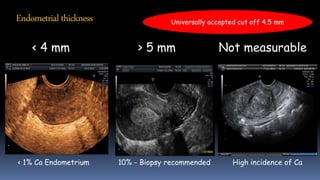

Endometrialthickness

< 4 mm > 5 mm Not measurable

< 1% Ca Endometrium 10% - Biopsy recommended High incidence of Ca

Universally accepted cut off 4.5 mm

Endometrialthickness < 4 mm> 5 mm Not measurable < 1% Ca Endometrium 10% - Biopsy recommended High incidence of Ca Universally accepted cut off 4.5 mm